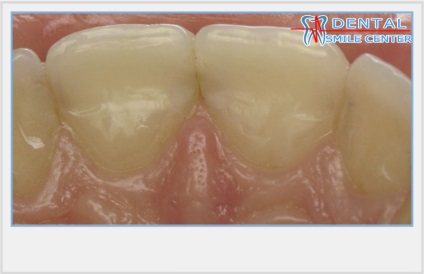

Az alakja a korona, a része az egyes elülső foga, látható, hogy a beteg és az emberek körül, alakított vesztibuláris által határolt felület egy vágóéi, nyak és két érintkező felületek. Anatómiailag a felső elülső fogak vannak elrendezve, mint egy rajongó, így eltérnek a felülről lefelé, hanem a fogazat fogainak koronák a benyomást kelti, hogy közelednek. Ez az illúzió által létrehozott aszimmetria koronák, más néven a jele a korona szög. Klinikailag szerint ez a funkció tetőpontján nyak metszőfogak és szemfogak távközzel helyezkedik el a középső sor a korona laterális, oldalsó metszőfogak több lekerekített sarkok, mint a medialis és a felső könnyezés halmok szemfogak mediálisan elmozdult a központtól a korona. Az ilyen kifejezett aszimmetria a nyak és a vágóél a felső elülső fogak koronák és egyesítjük az aszimmetria az érintkező felületek: valamennyi oldalirányú felületek jobban domború, mind mediális felszínével - közvetlenebb.

Annak ellenére, hogy két szomszédos korona szemközti fogak különböző magasságú, a vele érintkező pont az érintkező felületek találhatók ugyanazon a szinten. Ez az eljárás biztosítja a fogazat különböző konvex medialis és laterális / távoli felületek. Fang, kivételt képeznek az egymást követő csökkenése a magassága a fogak korona, az integráció a fogsor által nyújtott speciális formája. Másrészt, a különböző domborulata az érintkező felületek a fogak vezet az a tény, hogy a korona a felső metszőfogak helyzetben laterális és mediális kapcsolattartó pontok különbözik függőlegesen körülbelül I mm oldalsó felületén - közelebb a nyakát a fogak, a mediális felszínén - közelebb áll az élvonalbeli .

Ennek eredményeként, az érintkezési pontok az elülső felső fogak vannak elrendezve egy ív, megismételve a helyzetben a vágóélek vagy meghajlítjuk a felső széle az alsó ajak. Az alábbiakban, mind a felső fogazat a kapcsolattartó pont a kettő között metszőfogak.

A kapcsolattartó pontok között, a felső elülső fogak elrendezve egy görbe mentén, megismételve a hajlam a vágóélek a felső és alsó ajak kontúr. Ha az érintkezési pont között a metszőfogak és a szemfogak vetített középvonalában, akkor hogy három szinten egy pályát körülbelül 1 mm.

Található egy ív mentén, a felső elülső fogak érintkeznek egymással csak orális felületeken, így fogközökbõl mindig legyen látható arci széle egybeesik a felület síkja terület gondolkodás, és ezért beeső fény és harmonikusan együtt. Hiánya metszőfogak a hajlamok olyan közös fény visszaverése orálisan (opistognatiya) vagy vesztibuláris (prognathia) vezet disbalance holisztikus felfogása a tervezési egység. Elmélkedés a fényviszonyok, így a fogak élénkebb és kifejezőbb észlelés mások nem csak abban az esetben könnyű fogakat, hanem ha a központi zóna reflexív fogak, mint homorú parabolatükörre vagy a felső oldalsó metszőfogak található a gépen a középső metszőfog, ha a trapéz alakú fogazat.